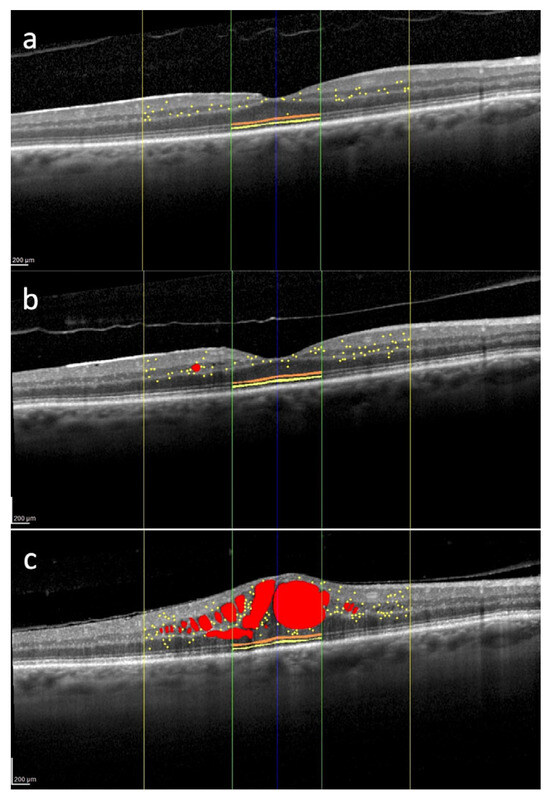

Hyperreflective retinal foci of inflammatory origin are increasingly recognized as valuable imaging biomarkers for the early detection of retinal neuroinflammation in radiation maculopathy and other macular disorders, including diabetic macular edema [20]. These foci typically appear as isolated, small-sized (<30 µm), moderately reflective spots—comparable to the reflectivity of the retinal nerve fiber layer (RNFL)—and are initially localized in the inner retinal layers. Importantly, they do not correlate with any identifiable anatomical structures on color fundus photography or en face OCT, such as blood vessels or lipid exudates. Current evidence suggests that these HRFs likely correspond to clusters of activated and proliferating microglial cells, thereby providing an in vivo indicator of localized retinal inflammation: (neuro)inflammatory HRF (I-HRF) [43]. Importantly, the number and spatial distribution of I-HRF tend to increase even before the clinical onset of macular edema, providing an opportunity for early detection of disease, as represented in Figure 2. The identification of I-HRF is not only helpful in diagnosing RM at a preclinical stage but also offers insights into the underlying inflammatory processes [16]. By tracking changes in I-HRF number over time, clinicians can monitor disease progression and potentially evaluate the efficacy of interventions aimed at reducing inflammation [16].

Figure 2. Overview of several spectral domain optical coherence tomography biomarkers evaluated in the macula of the right eye of a 62-year-old patient treated for uveal melanoma. The tumor was located in the inferior quadrant and classified as medium-sized. The patient underwent Iodine-125 plaque brachytherapy, with a total dose of 85 Gy delivered to the tumor apex. Intraretinal fluid (red); hyperreflective retinal foci (yellow dots) localized within the central 3 mm (yellow lines); external limiting membrane (orange) and ellipsoid zone (yellow) localized within the central 1 mm (green lines). 12 months after brachytherapy, hyperreflective retinal foci are 35, and they are mainly located in the inner retina (a). 24 months after treatment, there is an increase in the number of hyperreflective retinal foci with their progressive migration toward the outer retina (b). 30 months after brachytherapy, there is a further increase in the number of hyperreflective retinal foci with the appearance of center-involved macular edema (c). No treatment was administered between timepoints (b,c). Scale bar: 200 µm.